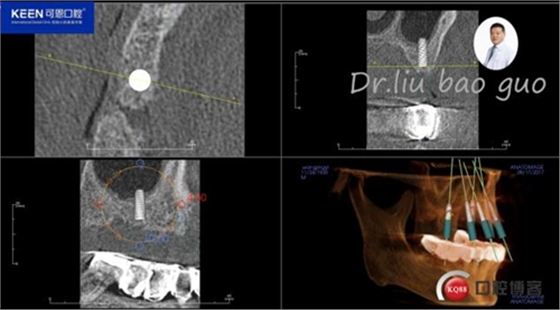

手術(shù)前種植軟件設(shè)計(jì)方案

數(shù)字化種植導(dǎo)板設(shè)計(jì)及制作